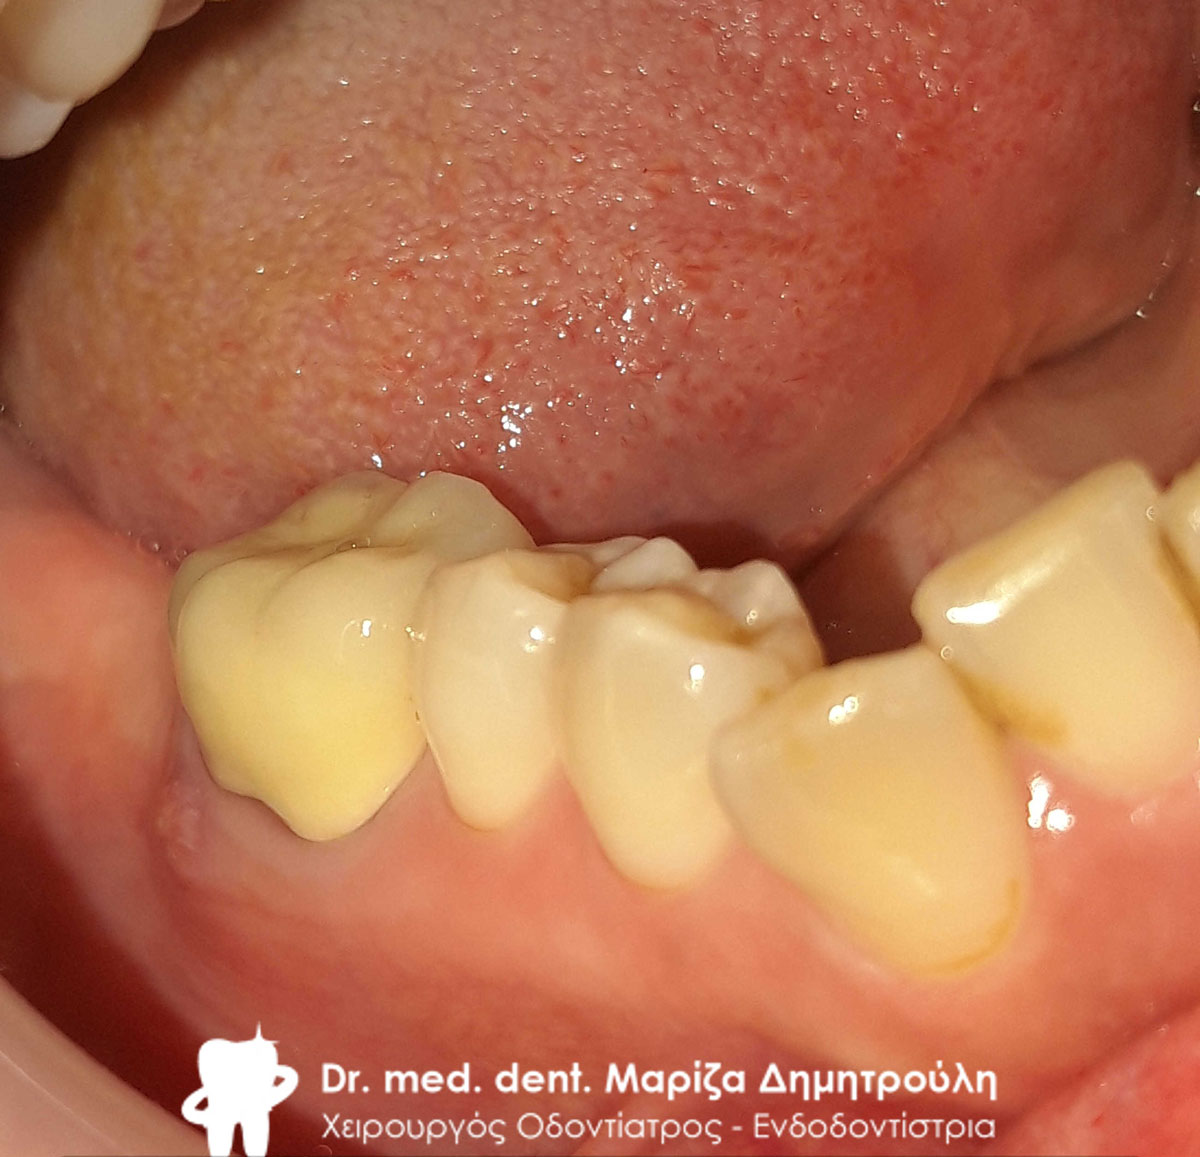

Περιστατικό – Ολοκεραμική στεφάνη / θήκη ζιρκονίου στην αριστερή πλευρά της κάτω γνάθου

Η ασθενής είχε ένα παλιό μαύρο σφράγισμα αμαλγάματος το οποίο την πονούσε. Μετά την κλινική και ακτινογραφική εξέταση του δοντιού αποφασίστηκε η αφαίρεση του παλιού σφραγίσματος, η νέα ανασύσταση και η κάλυψη του δοντιού με ολοκεραμική θήκη δοντιού, καθώς το οδοντικό έλλειμμα ήταν μεγάλο.

Αρχική κλινική εικόνα του δοντιού με το παλιό μαύρο σφράγισμα αμαλγάματος

Τελική εικόνα του δοντιού με τη νέα ολοκεραμική στεφάνη